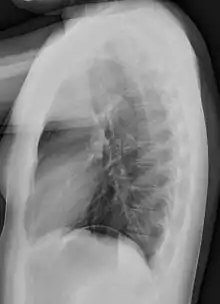

In anteroposterior (AP) views, the positions of the x-ray source and detector are reversed: the x-ray beam enters through the anterior aspect and exits through the posterior aspect of the chest. AP chest x-rays are harder to read than PA x-rays and are therefore generally reserved for situations where it is difficult for the patient to get an ordinary chest x-ray, such as when the patient is bedridden. In this situation, mobile X-ray equipment is used to obtain a lying down chest x-ray (known as a "supine film"). As a result, most supine films are also AP.

Lateral views of the chest are obtained in a similar fashion as the posteroanterior views, except in the lateral view, the patient stands with both arms raised and the left side of the chest pressed against a flat surface.

Typical views

Required projections can vary by country and hospital, although an erect posteroanterior (PA) projection is typically the first preference. If this is not possible, then an anteroposterior view will be taken. Further imaging depends on local protocols which is dependent on the hospital protocols, the availability of other imaging modalities and the preference of the image interpreter. In the UK, the standard chest radiography protocol is to take an erect posteroanterior view only and a lateral one only on request by a radiologist.[5] In the US, chest radiography includes a PA and Lateral with the patient standing or sitting up. Special projections include an AP in cases where the image needs to be obtained stat (immediately) and with a portable device, particularly when a patient cannot be safely positioned upright. Lateral decubitus may be used for visualization of air-fluid levels if an upright image cannot be obtained. Anteroposterior (AP) Axial Lordotic projects the clavicles above the lung fields, allowing better visualization of the apices (which is extremely useful when looking for evidence of primary tuberculosis).